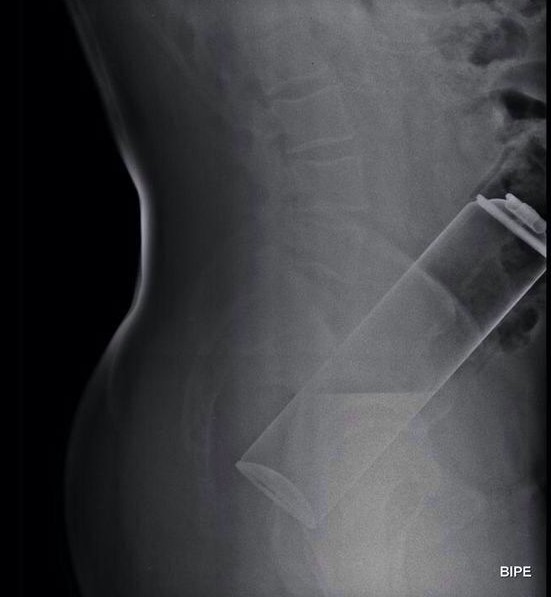

Diagnosis is made by directed questioning, physical examination and digital rectal examination. Laboratory tests, plain abdominal X-ray, CT scan and/or fibrocolonoscopy will also be performed.